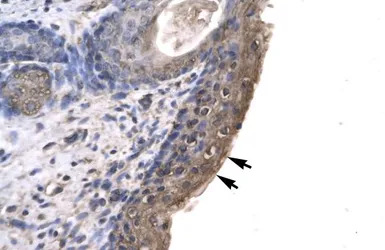

IHC-P analysis of human spermatophore tissue using GTX77821 RNF12 antibody at 4.0-8.0μg/ml.